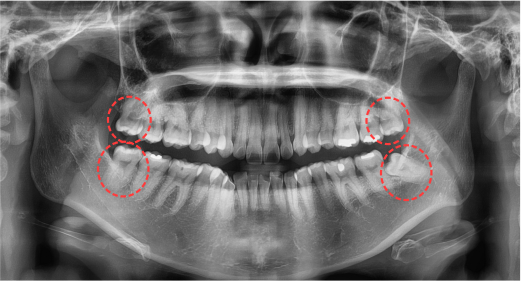

사랑니가 턱뼈 안에서 뿌리가 형성되고 맹출이 되는 것은 파노라마 또는 3D CT로 확인할 수가 있는데, 사랑니의 맹출방향이 불량할 것으로 예상되는 경우에는 예방적으로 발치를 하는 것이 좋습니다.

사랑니 발치 Before & After